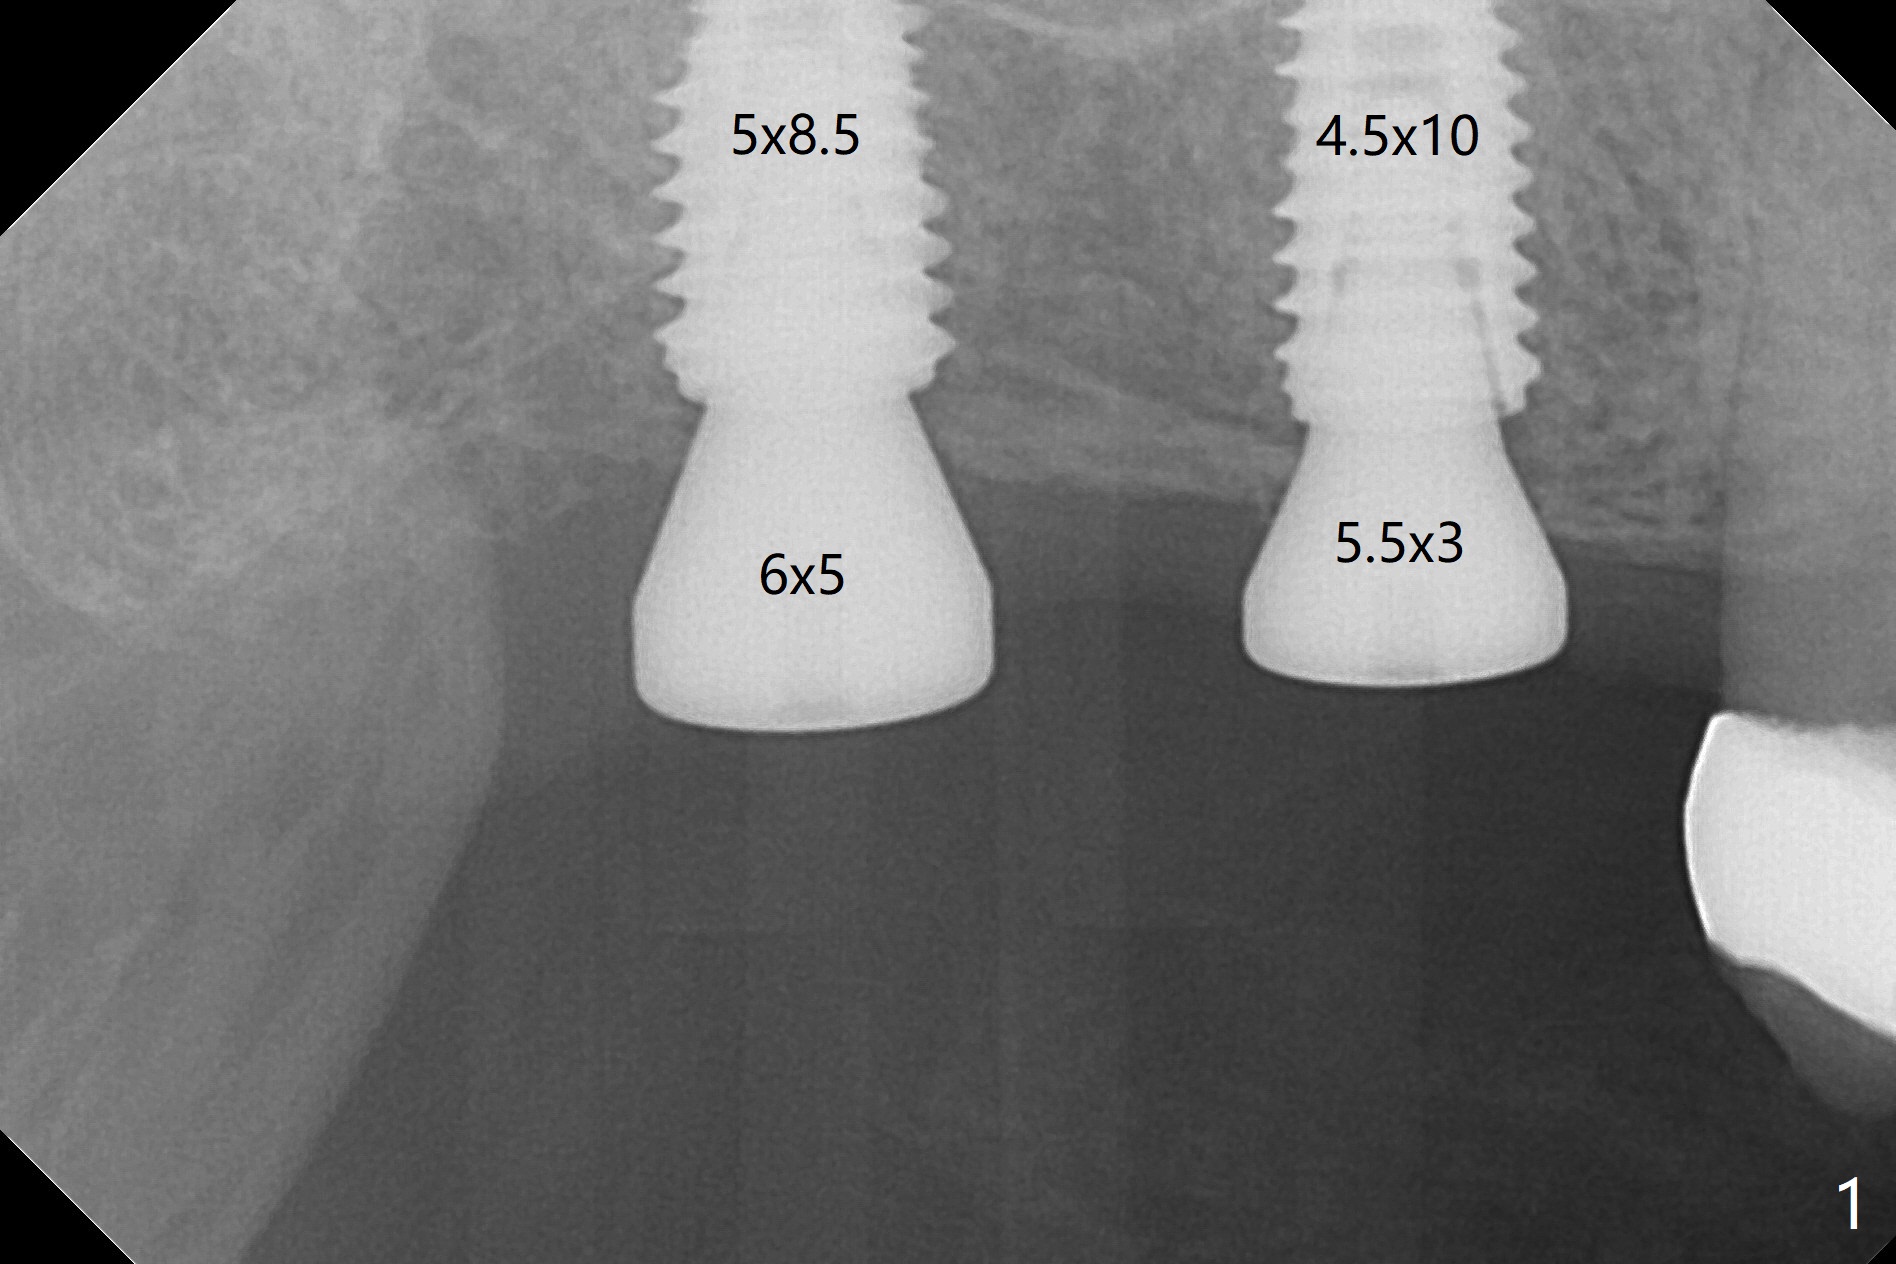

Osteotomy at the sites of #2 and 3 goes on as planned. Sinus lift using DIO 2.8 mm round bur with 6 and 7 mm stoppers (respectively) is carried on without certainty, because it is difficult to feel the stop through the osteotomy. The crest may be uneven or soft. It appears that the soft tissue landmark as a stop may be easier to identify. In fact a 3 mm IBS Magic Expander (an osteotome) was used for sinus lift at #3. The 2 implants are placed with 20 and 30 Ncm (Fig.1,2). Healing abutments are inserted. At 2-week follow-up, the patient reports "pain a few days earlier, took a pill of antibiotic, pain gone. UR metal is sharp". She does not take antibiotic regularly. Exam reveals that there is heavy plaque around #2,3 healing abutments. The buccal edge of #2 abutment is trimmed for comfort. Nearly 1 month postop, #3 healing abutment dislodges with buccal gingival erythema and edema with purulent discharge (Fig.3). Healing screw is placed at #3 with Amoxicillin and Chlorhexidine prescribed. One week later, the implant at #3 turns when the healing screw is retightened (Fig.4). After debridement, Vanilla graft is placed. There is no infection at #2 or 3 four months postop (Fig.5,6); the lingual gingiva is erythematous and edematous at #29 with mobility II (Fig.7 (vertical root fracture)). Uncover is conducted at the site of #3; there is no infection superficial 7.5 months postop (Fig.8). There is a large buccal defect upon incision with dark hemorrhage. In fact the bone density is low crestally (Fig.8 *). Bone graft is placed for the 2nd time. Eleven months later (1.5 years post implant placement), the bone regrows crestal (Fig.9 *). The crown at #3 is loose 1 year 5 months post cementation (Fig.10). After proximal trimming (Fig.11 *), the abutment at #3 is seated completely. After lab repair, crown oral cement, crown/abutment removal for excess cement removal, the crown/abutment cannot be torqued >25 Ncm (Fig.12, 30 Ncm). PA shows incomplete seating (Fig.12 <). Then the crown is sectioned so that the abutment has more freedom to be seated completely with pressure against the gingiva (the patient feels pain, Fig.13). Torque is 30 Ncm. After crown cementation, the abutment will not be removed for cement removal.